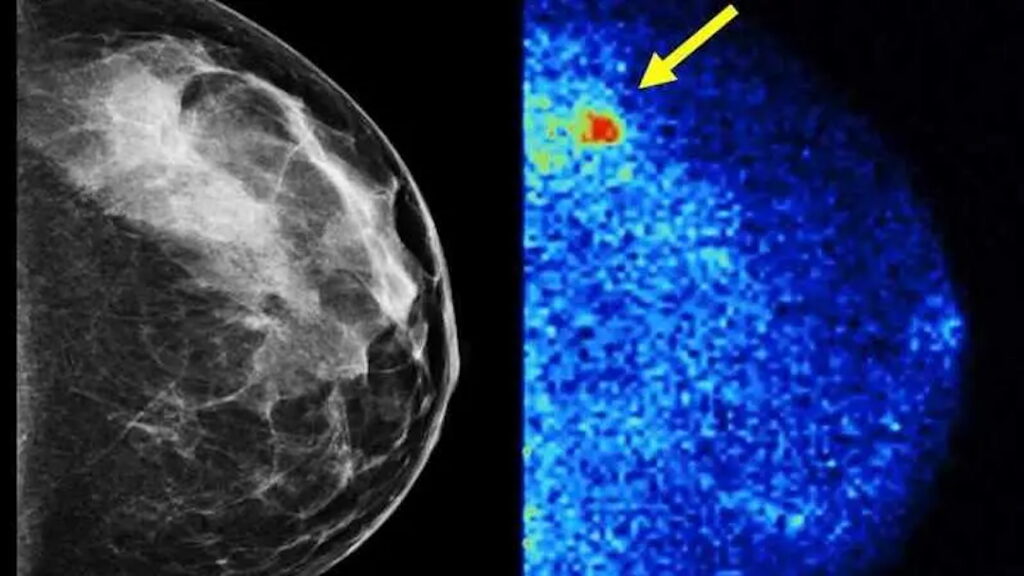

Un estudio de Mayo Clinic revela que añadir Imagen Molecular de la Mama (MBI) a la mamografía 3D más que duplica la detección de cáncer en mujeres con tejido mamario denso, una limitación del cribado tradicional.

La detección precoz es fundamental para la supervivencia al cáncer de mama. Sin embargo, la mamografía, la principal herramienta de cribado, tiene una limitación significativa: la dificultad para identificar tumores en mujeres con tejido mamario denso. Este tipo de tejido, que afecta a casi la mitad de las mujeres de 40 años o más que se someten a mamografías , puede ocultar los cánceres , retrasando su diagnóstico hasta alcanzar un tamaño avanzado.

Una nueva investigación, dirigida por expertos de Mayo Clinic y publicada en la revista «Radiology«, arroja luz sobre una solución prometedora: la Imagen Molecular de la Mama (MBI). El estudio multicéntrico halló que añadir esta prueba a la mamografía 3D (tomosíntesis digital) más que duplicó la detección del cáncer en mamas densas.

La Imagen Molecular de la Mama (MBI) es una técnica de medicina nuclear que utiliza un detector de rayos gamma para analizar la función de la mama y cómo están cambiando las células, a diferencia de la mamografía que solo examina la anatomía. A la paciente se le administra una inyección de una cantidad muy pequeña de un trazador radioactivo, un compuesto que se dirige a las células que se están dividiendo rápidamente y a las áreas con aumento del flujo sanguíneo. Unos minutos después, se obtienen imágenes de la mama.

La doctora Hruska detalla que este trazador, muy común y con un perfil de riesgo bajo, ha sido utilizado en imagenología cardíaca desde los años 90. La tecnología MBI emplea un detector pequeño, hecho de tecnología de semiconductores, que puede colocarse directamente sobre la mama, lo que permite una mejor resolución espacial para detectar tumores pequeños.

Los resultados fueron contundentes: al añadir MBI a la mamografía, se detectaron más de dos veces y media más cánceres de mama invasivos en mujeres con mamas densas. Los radiólogos especialistas en mamas detectaron más tejido canceroso con las pruebas combinadas que con cualquiera de las técnicas por separado.

«Otra forma de verlo es que nuestro cribado de rutina con mamografía está dejando pasar más de la mitad de los cánceres de mama que realmente estaban allí», afirma la doctora Hruska en una conferencia en la que participó Vida y Futuro. La mayoría de los cánceres adicionales detectados con MBI se consideraron clínicamente importantes, ya que eran invasivos, de tamaño considerable y un 20% estaban avanzados. La meta es incorporar el cribado antes para evitar que estos cánceres avanzados se manifiesten.